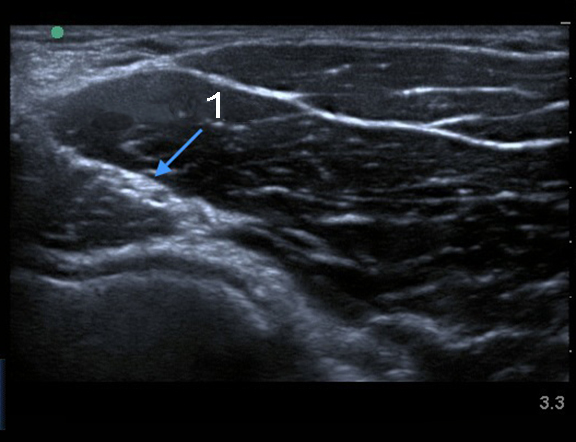

肘橈骨神経の画像

橈骨神経